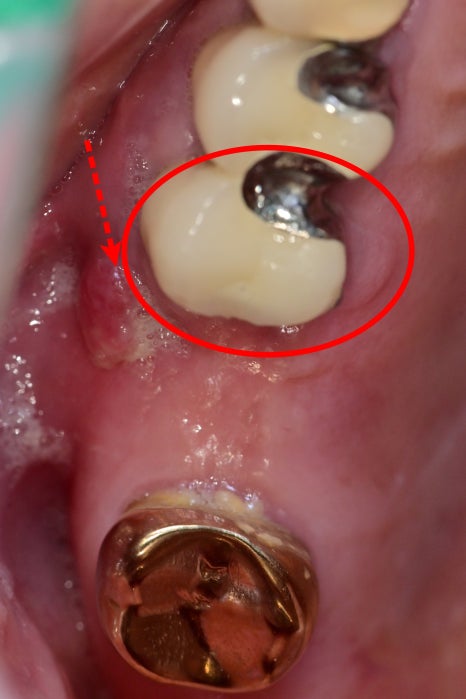

잇몸에 뭐가 튀어나오고 염증 같아요

치과 앞을 지나가시다가 우연찮게 내원해 주신 어르신입니다.

고리를 거는 힘을 받는 앞 치아 뿌리 쪽에 염증이 생기고

그 염증이 잇몸 바깥으로 염증 주머니를 만들어서 불편감을 일으키고 있었습니다.